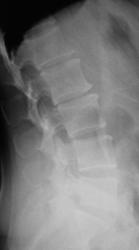

Пол пациента: Женский пол Тип патологии: Другое Область исследования: Скелетно-мышечная система Методы исследования: Rg Боли в пояснице, пациентка направлена на рентгенографию ПОП https://radiomed.ru/sites/default/files/styles/case_slider_image/public/user/12/2.dscn1426a.jpg?itok=e7leiWEL https://radiomed.ru/sites/default/files/styles/case_slider_image/public/user/12/3.dscn1427.jpg?itok=VzSynAjt https://radiomed.ru/sites/default/files/styles/case_slider_image/public/user/12/4.dscn1427a.jpg?itok=6MsG_uLx ID:27772 Чт, 11/04/2013 - 19:54 #1 Алексей Станисл... Не на сайте Был на сайте: 6 лет 3 дня назад Зарегистрирован: 11.08.2012 - 20:33 Публикации: 1903 Даже и боюсь сказать, такие баталии обычно по этому поводу - спондилолиз L4, L5? Не говоря о пресловутом остеохондрозе и "развороте" суставов L3-4, L4-5 во фронтальную плоскость...))) Но раз все молчат... С уважением, Пт, 12/04/2013 - 01:34 #2 Катенёв Валенти... Не на сайте Был на сайте: 7 лет 2 месяцев назад Зарегистрирован: 22.03.2008 - 22:15 Публикации: 54876 Алексей Станиславович wrote: Даже и боюсь сказать, такие баталии обычно по этому поводу А баталий вот и нет..., один Ваш коммент уважаемый коллега, и всё... Пт, 12/04/2013 - 08:35 #3 Алексей Станисл... Не на сайте Был на сайте: 6 лет 3 дня назад Зарегистрирован: 11.08.2012 - 20:33 Публикации: 1903 Не знаю, я столько "красных тряпок" накидал... Неужели все правильно (и больше ничего не видно)? С уважением, Пт, 12/04/2013 - 17:57 #4 Катенёв Валенти... Не на сайте Был на сайте: 7 лет 2 месяцев назад Зарегистрирован: 22.03.2008 - 22:15 Публикации: 54876 Алексей Станиславович wrote: Но раз все молчат... Значит тайну великую хранят...

Даже и боюсь сказать, такие баталии обычно по этому поводу - спондилолиз L4, L5? Не говоря о пресловутом остеохондрозе и "развороте" суставов L3-4, L4-5 во фронтальную плоскость...